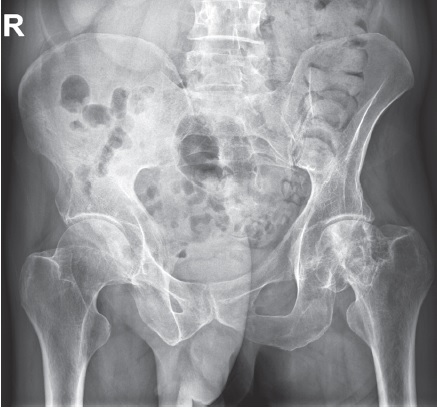

On admission, the local status revealed a pain syndrome (6 points according the VAS) aggravated by active and passive movements. The patient used a crutch for walking and exhibited significant limping. There was a relative shortening of the left lower limb by 2 cm. No redness or swelling was observed in the left hip joint area, and local temperature was not elevated. Thigh muscle atrophy was present, measuring 3 cm compared to the contralateral side. The patient reported temporary relief from non-steroidal anti-inflammatory drugs. X-rays, CT, and MRI showed signs of stage 3B (late) aseptic necrosis of the left femoral head according to the ARCO classification (Fig. 1, 2).

Fig. 1. Clinical case 1. X-ray of the pelvis in frontal projection: osteonecrosis of the left femoral head — stage 3B (late) according to the ARCO classification